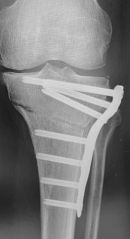

高位脛骨骨切り術OWHTO

人工膝関節

単顆置換術UKA

置換術(MA法)MA TKA

置換術(KA法)KA TKA